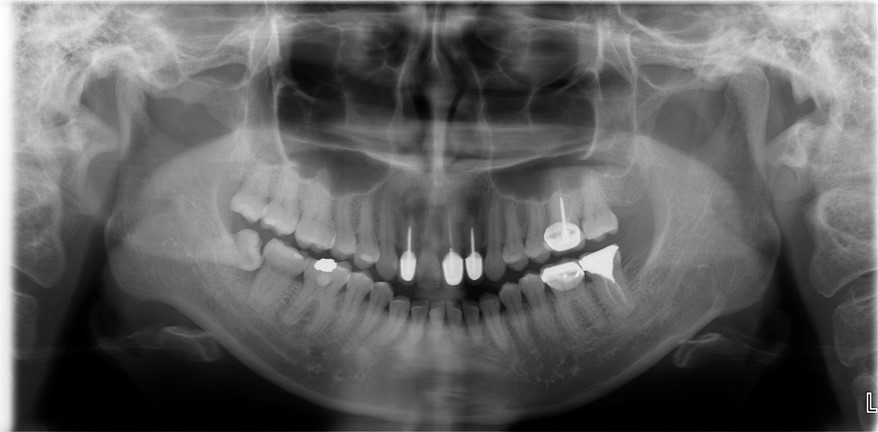

治療前,前牙根管治療不完全

根管治療6個月後,仍有根尖病變

阻生齒拔除,骨膠原修復